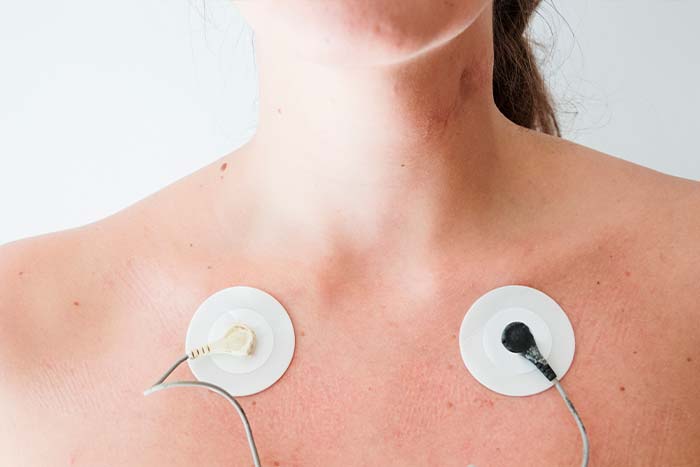

Ein EKG ist ein wichtiger Test zur Beurteilung Ihrer Herzgesundheit. Wir bieten diese Untersuchung an, um Herzprobleme frühzeitig zu erkennen.